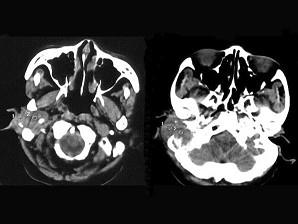

问题 女,56岁,右侧中耳术后发现右外耳道新生物一年,PE:右外耳道内段被新生物充满,CT如图所示,应诊断为 ( )

选项 A、听神经瘤 B、中耳结核 C、中耳癌 D、颈静脉球瘤 E、胆脂瘤

答案 C